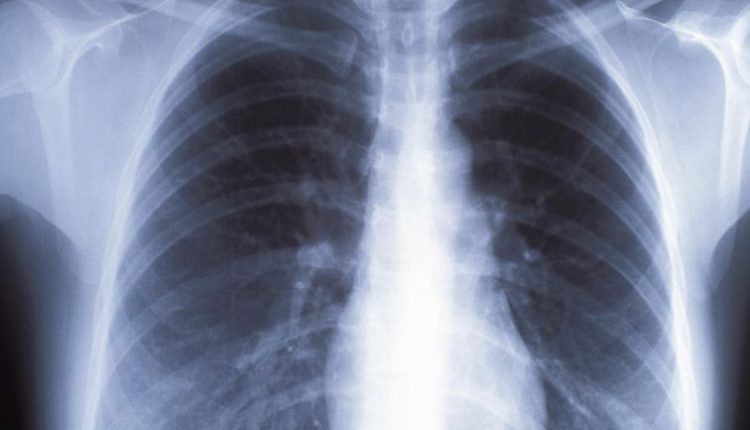

The number increased significantly from 2018, which coincides with Microsoft ending support for Windows 7 earlier this year. A significant number of machines run even older operating systems, including Windows XP, which Microsoft stopped supporting in 2014. The imaging devices include machines that take X-rays, MRIs, mammograms and CAT scans.